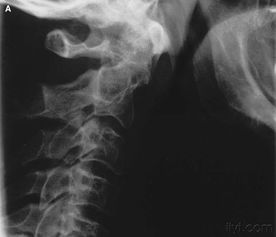

因為頸骨骨折也就是頸部脊椎骨的骨 折,在脊椎骨中央有神經(jīng)通過,這些神經(jīng)像電纜一樣能把大腦的命令傳達到全身,又能把身體的感覺傳向大腦。如果骨折切斷或壓迫脊椎骨中的神經(jīng),頸以下就會完 全麻痹,有時會使呼吸停止。

3、頸椎骨折常見于跳水誤跳入淺游泳池,或從很高的地方墜落以及交通事故等。